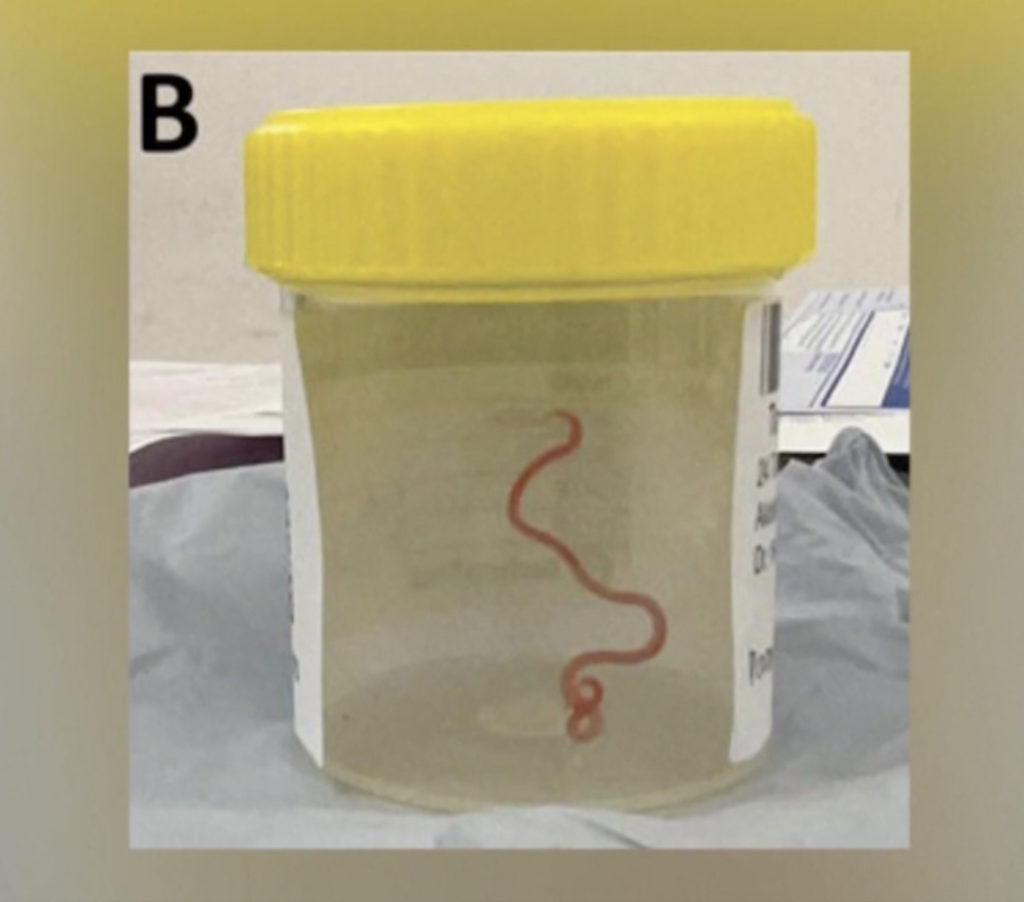

The revelation sparked intense curiosity among medical professionals to identify the parasite.

Dr. Sanjaya Senanayake, an infectious disease expert at Canberra Hospital, recounted, One colleague in the hospital lab was able to reach an animal parasitology expert at a governmental scientific research agency just 20 minutes away – and found their unexpected answer.

“We were able to send the live wiggling worm to him, and he was able to look at it and immediately identify it.”

The parasite was identified as Ophidascaris Robertsi, a roundworm typically found in pythons, after a thorough examination and molecular tests.